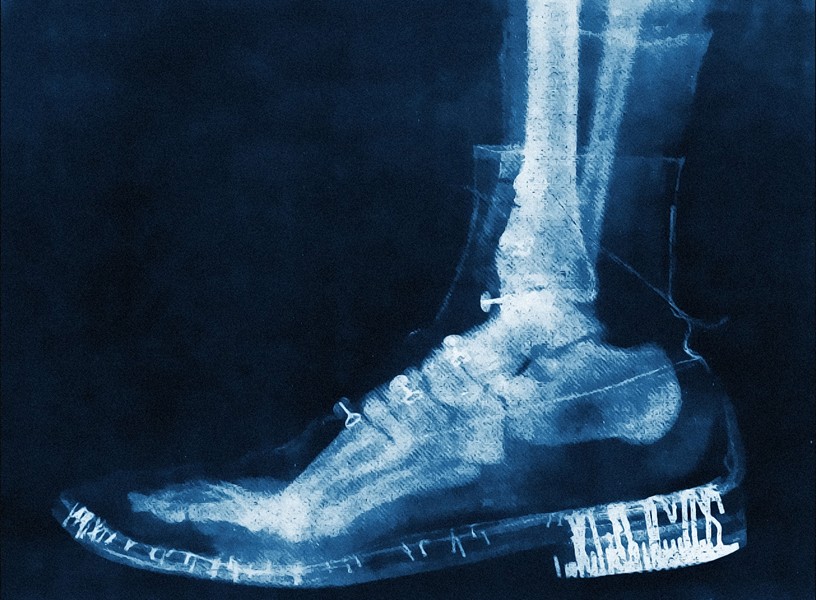

Early X-ray of a foot inside a shoe

By M. Nardi, after Arthur Honoré Radiguet (1850–1905)

No. 2045 Musée Radiographique Radiguet

Arthur Honoré Radiguet was a French physicist, engineer, optician, and photographer known for his groundbreaking work in developing scientific instruments, including early X-ray equipment. Building on his family’s legacy in optics and specialising in microscopes and loupes, he founded the company Radiguet et Massiot, which produced devices for radiography—an emerging field inspired by Wilhelm Röntgen's discovery of X-rays in 1895. In 1896, Radiguet became a leading French manufacturer, distributor, and photographer of X-ray technology, compiling his creations into the Musée Radiographique Radiguet. Early experiments with this technology, such as his X-ray of a foot inside a shoe, likely created for scientific demonstration or educational purposes, demonstrated its ability to penetrate materials and reveal internal structures. Despite his remarkable contributions, Radiguet's dedication came at a personal cost, as radiation poisoning ultimately claimed his life in 1905. Despite the tragic end, Radiguet's contributions remain vital, earning him acclaim as a pioneer of French radiography and leaving behind invaluable X-ray photographs as testaments to a transformative era in scientific history.